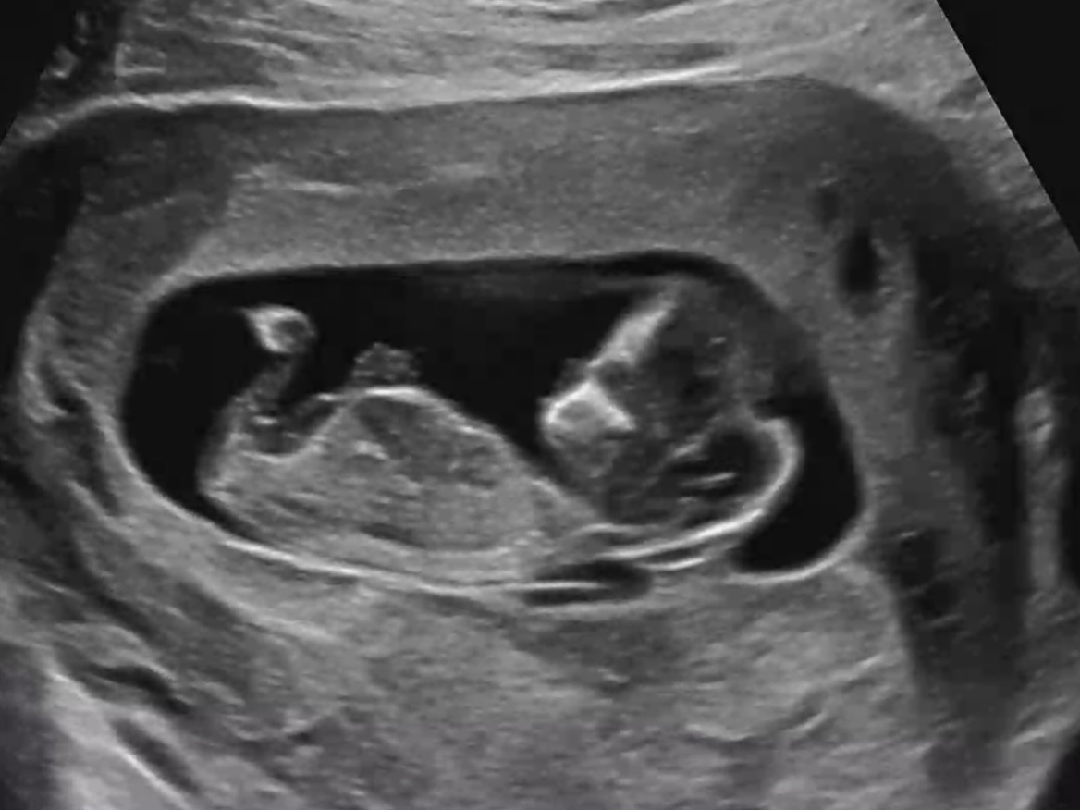

12주차 고수님들 각도법 도움 부탁드려요^^(모찌파파)

안녕하세요..^^ 고수님들 각도법 부탁드립니다~~~~!! 모두 건강하고 행복하십쇼!

초음파로도 오똑한 콧날이 보여서요. 아기가 부럽네요😁

아기 콧대가 예쁘네요. 생식기 돌기는 잘 안보이네요.